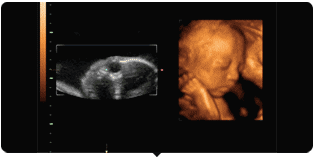

相比于普通B超抽象而又模糊的黑白图像,

四维彩超的图片,

让准爸妈们,

第一次看清了腹中宝宝的“模样”